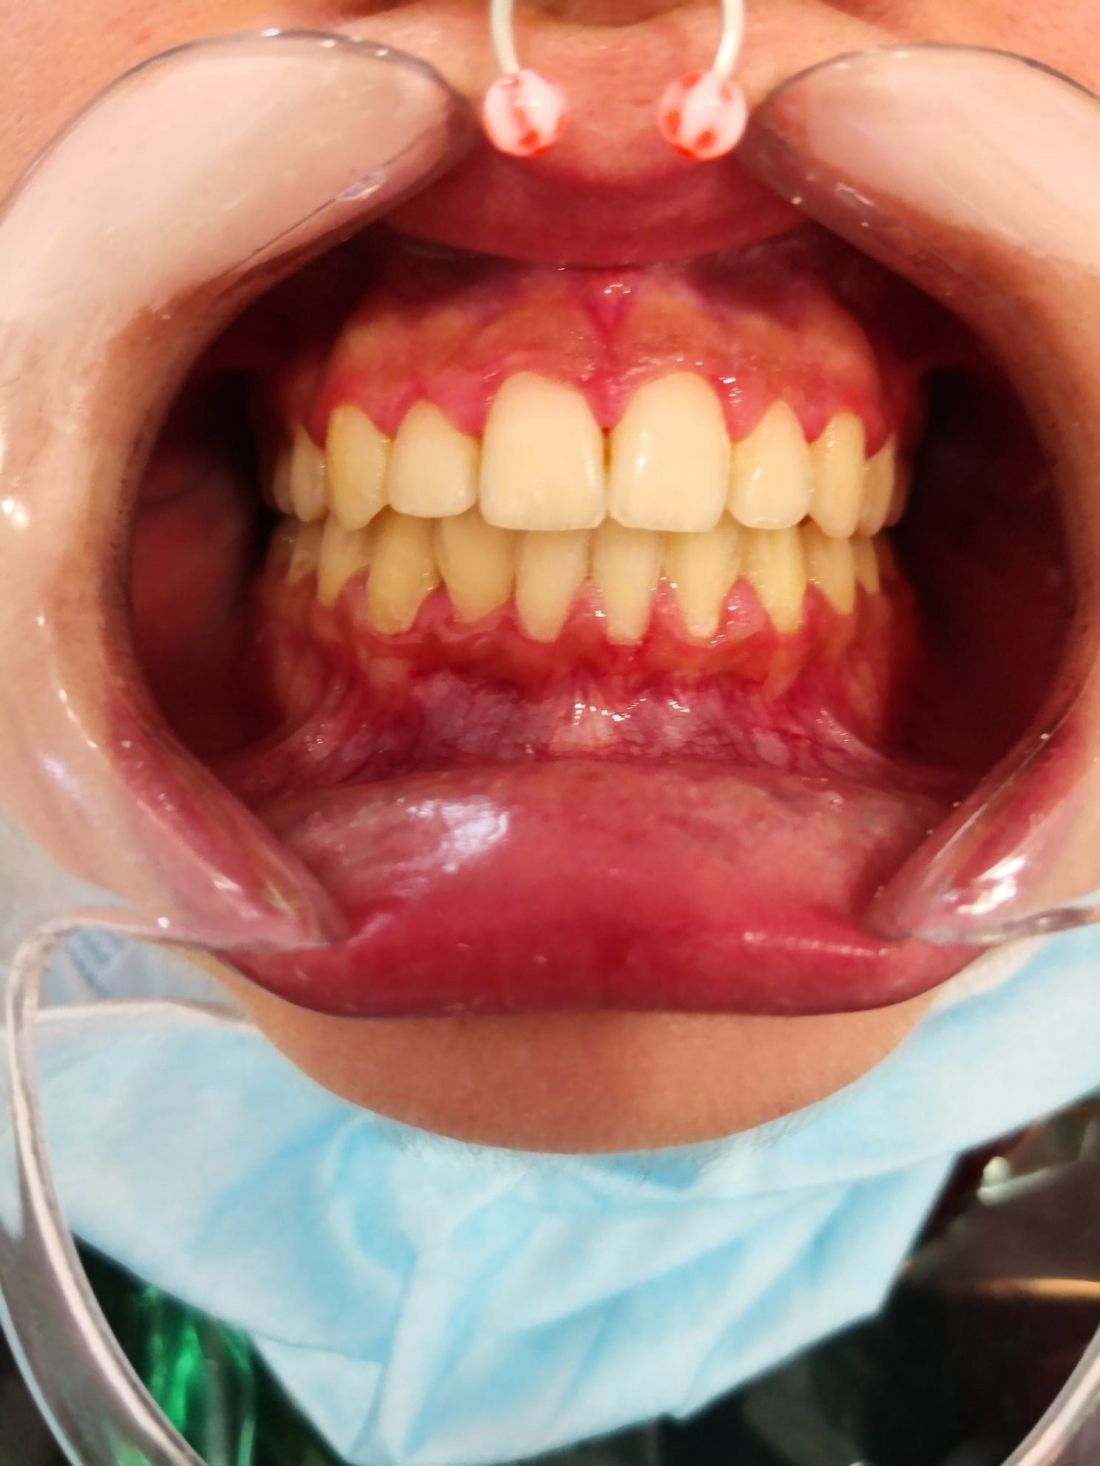

Ortopedia ortodoncia transposición